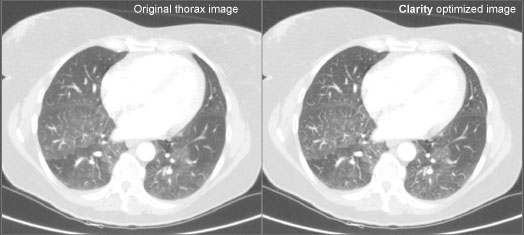

A comparison of the original and Clarity-enhanced CT image from Philips Brilliance 64, showing a 3 mm contrast-enhanced thorax slice at 133 mAs, 120 KVP.

The facility used the Clarity CT Solution software made by Saphenia. The system was connected to the facility’s Philips Brilliance 64 CT and Siemens PACS. Data acquired from the scanner were reconstructed on the scanner before post-processing on the Clarity server. From there DICOM images were transferred to the PACS and Philips workstation. In addition, unprocessed raw data was transferred to the workstation for comparison and secondary reconstruction purposes.